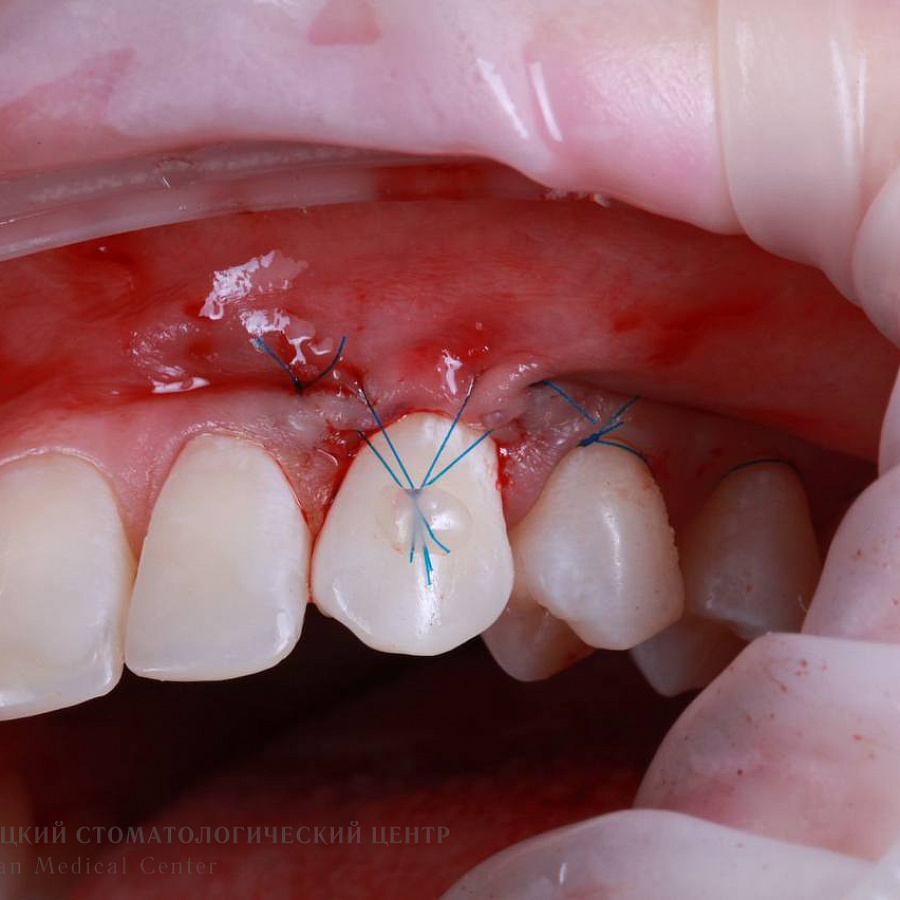

Рецессия десны

Этапы лечения

Пациенту провели рецессию десны.